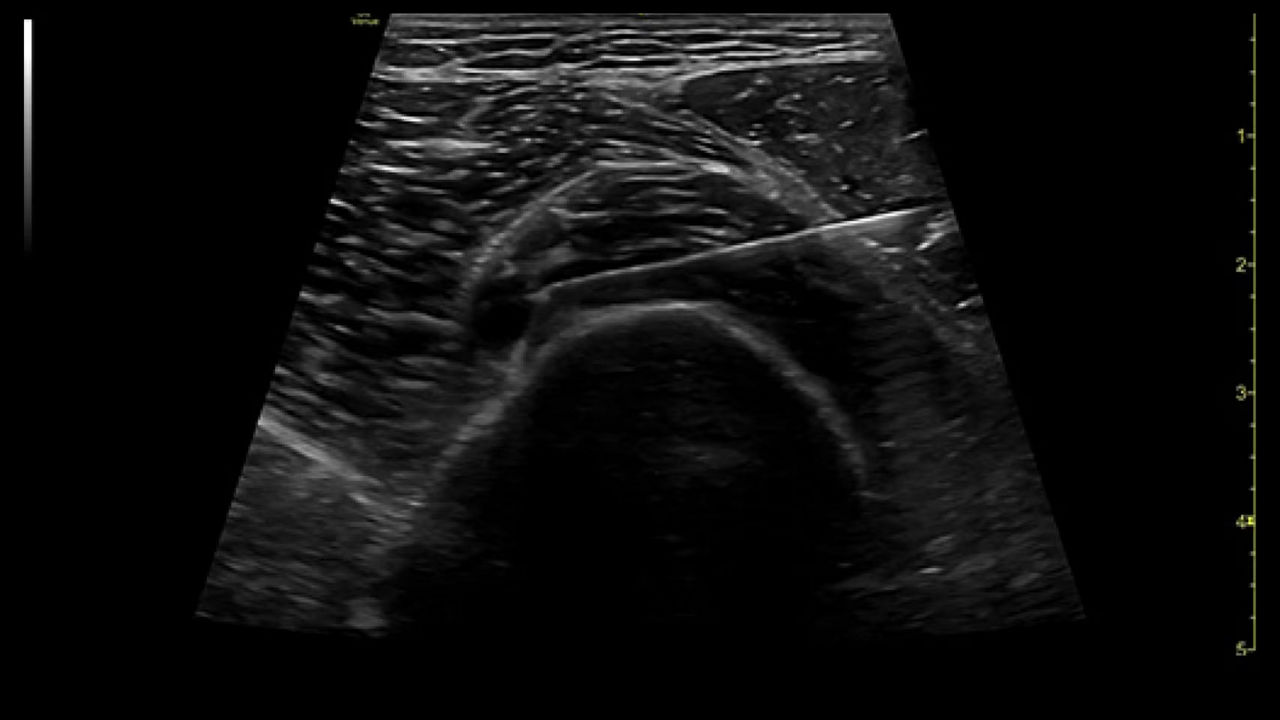

Precision Needle Guidance

Accurately guide and visualize injections

Even in the most experienced hands, blind injections—those performed without imaging—are not 100% accurate. By using ultrasound for needle guidance, the needle is highlighted and you have quality visualization of joints and soft tissue during procedures at a lower acquisition cost than other imaging modalities.

Excellent visualization with Needle Mode

Needle Mode also allows you to easily differentiate between the needle and patient anatomy with confidence—allowing you to quickly guide the needle exactly where it needs to be and helping to minimize patient discomfort.